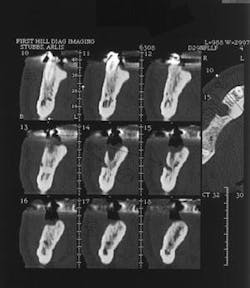

Figure 12 - CT scan demonstrating insufficient bone for implants (SimPlant software)